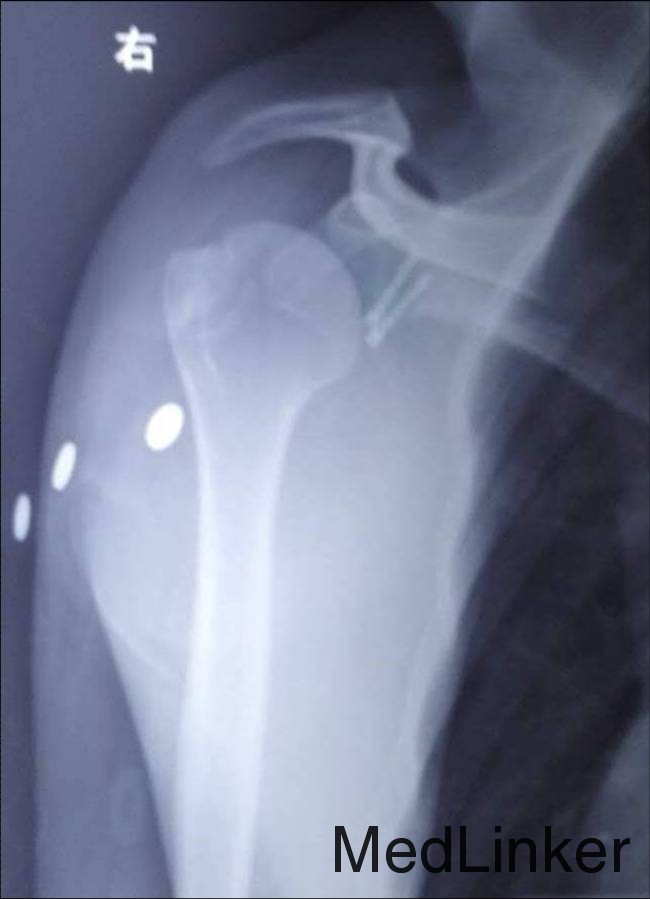

右侧臂丛神经阻滞麻醉 右肩关节前路切开复位螺钉内固定术 术后12日右上肢悬吊固定